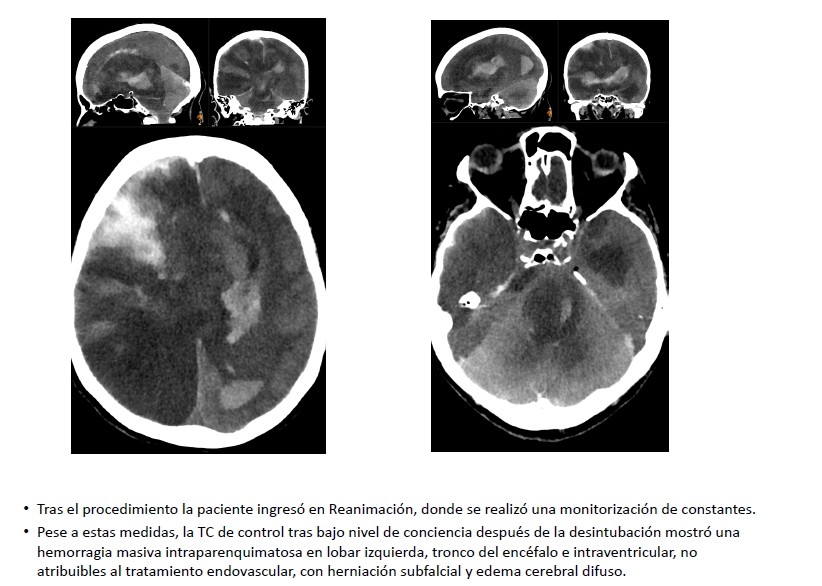

Complicación hemorrágica masiva tras trombectomía mecánica con aspiración en paciente añosa con antecedente neoplásico